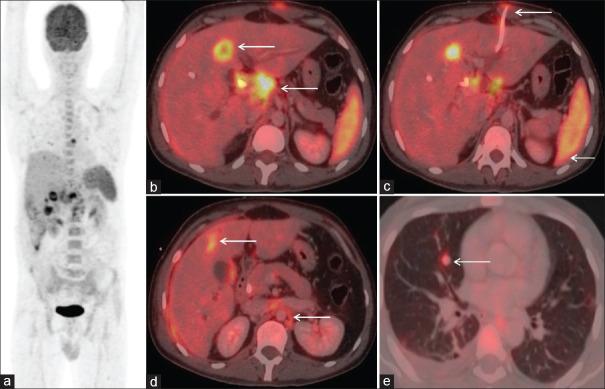

Role of FDG PET/CT in evaluation of biliary tract diseases remains relatively unexplored. PET/CT with FDG helps in evaluation of both infective / inflammatory as well as neoplastic diseases as increased glucose utilization is observed in both the conditions. In this article, we describe the spectrum of FDG PET/CT findings in various diseases affecting the biliary tract. Role of FDG PET/CT in neoplastic diseases involving the biliary duct has been described at the time of staging and response evaluation; in characterization of the intrahepatic mass (abscess v/s cholangiocarcinoma). In addition, we have discussed about the false positive FDG uptake along the biliary duct stent, which interfere with scan interpretation. Few of the benign conditions described are Langerhans cell histiocytosis and IgG4 related disease involving the biliary duct and adenomyomatosis and Xanthogranulomatous cholecystitis involving the gall bladder.

氟代脱氧葡萄糖正电子发射断层显像/计算机断层扫描(FDG PET/CT)在胆道疾病评估中的作用仍相对未被充分探索。含氟代脱氧葡萄糖的PET/CT有助于评估感染性/炎症性疾病以及肿瘤性疾病,因为在这两种情况下均观察到葡萄糖利用率增加。在本文中,我们描述了FDG PET/CT在影响胆道的各种疾病中的表现谱。FDG PET/CT在胆管肿瘤性疾病分期和疗效评估以及肝内肿块(脓肿与胆管癌)鉴别诊断中的作用已被阐述。此外,我们还讨论了沿胆管支架出现的FDG摄取假阳性情况,这会干扰扫描结果的解读。所描述的一些良性疾病包括累及胆管的朗格汉斯细胞组织细胞增多症和IgG4相关疾病,以及累及胆囊的腺肌增生症和黄色肉芽肿性胆囊炎。